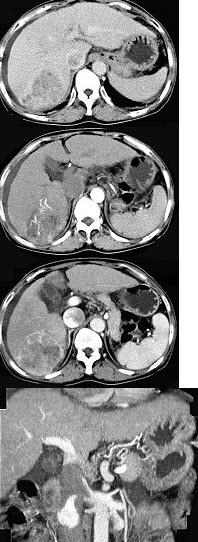

女性,55岁,曾患乙肝,肝硬化多年,右上腹胀痛1月余,CT检查如图所示,最可能的诊断是( )

A:肝硬化腹水、下腔静脉血栓形成

B:肝硬化腹水、胆管细胞癌

C:肝硬化腹水、肝癌并下腔静脉癌栓

D:肝硬化腹水、肝脓肿

E:肝硬化腹水、肝血管瘤